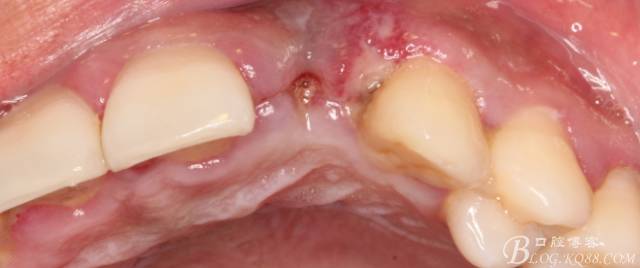

10天拆線一切正常,又過(guò)了兩周患者復(fù)診,自述期間無(wú)異常??趦?nèi)檢查,真的嚇了一跳,唇側(cè)鼓了個(gè)包,擠壓有白色分泌物溢出,絕對(duì)不是膿液,液體排除后,術(shù)區(qū)觸診空虛,外觀塌陷。這時(shí)候考研大夫的時(shí)刻到了,是先觀察一段時(shí)間再說(shuō)?還是馬上進(jìn)行處理?我的回答是:馬上處理!如果你沒(méi)有及時(shí)處理,而是放患者回家觀察,那么接下來(lái)會(huì)發(fā)生如下情況:1.回家后患者家屬及親友會(huì)有很多你可以想象得到的討論;2.患者及家屬會(huì)對(duì)你產(chǎn)生不信任,勢(shì)必會(huì)到其他門診或醫(yī)院檢查,他院大夫會(huì)不會(huì)發(fā)表對(duì)你不利的言論;3甚至?xí)蚁嚓P(guān)法律界人士找你討要說(shuō)法。

于是我果斷告知患者,手術(shù)失敗了,不能拖延,如不及時(shí)處理,炎癥繼續(xù)發(fā)展會(huì)很快波及鄰牙牙槽骨?;颊呓邮芪业慕ㄗh。切開(kāi)翻瓣,骨粉及生物膜消失了,骨吸收嚴(yán)重,幸運(yùn)的是,因?yàn)樘幚砑皶r(shí),鄰牙骨支持依然存在。